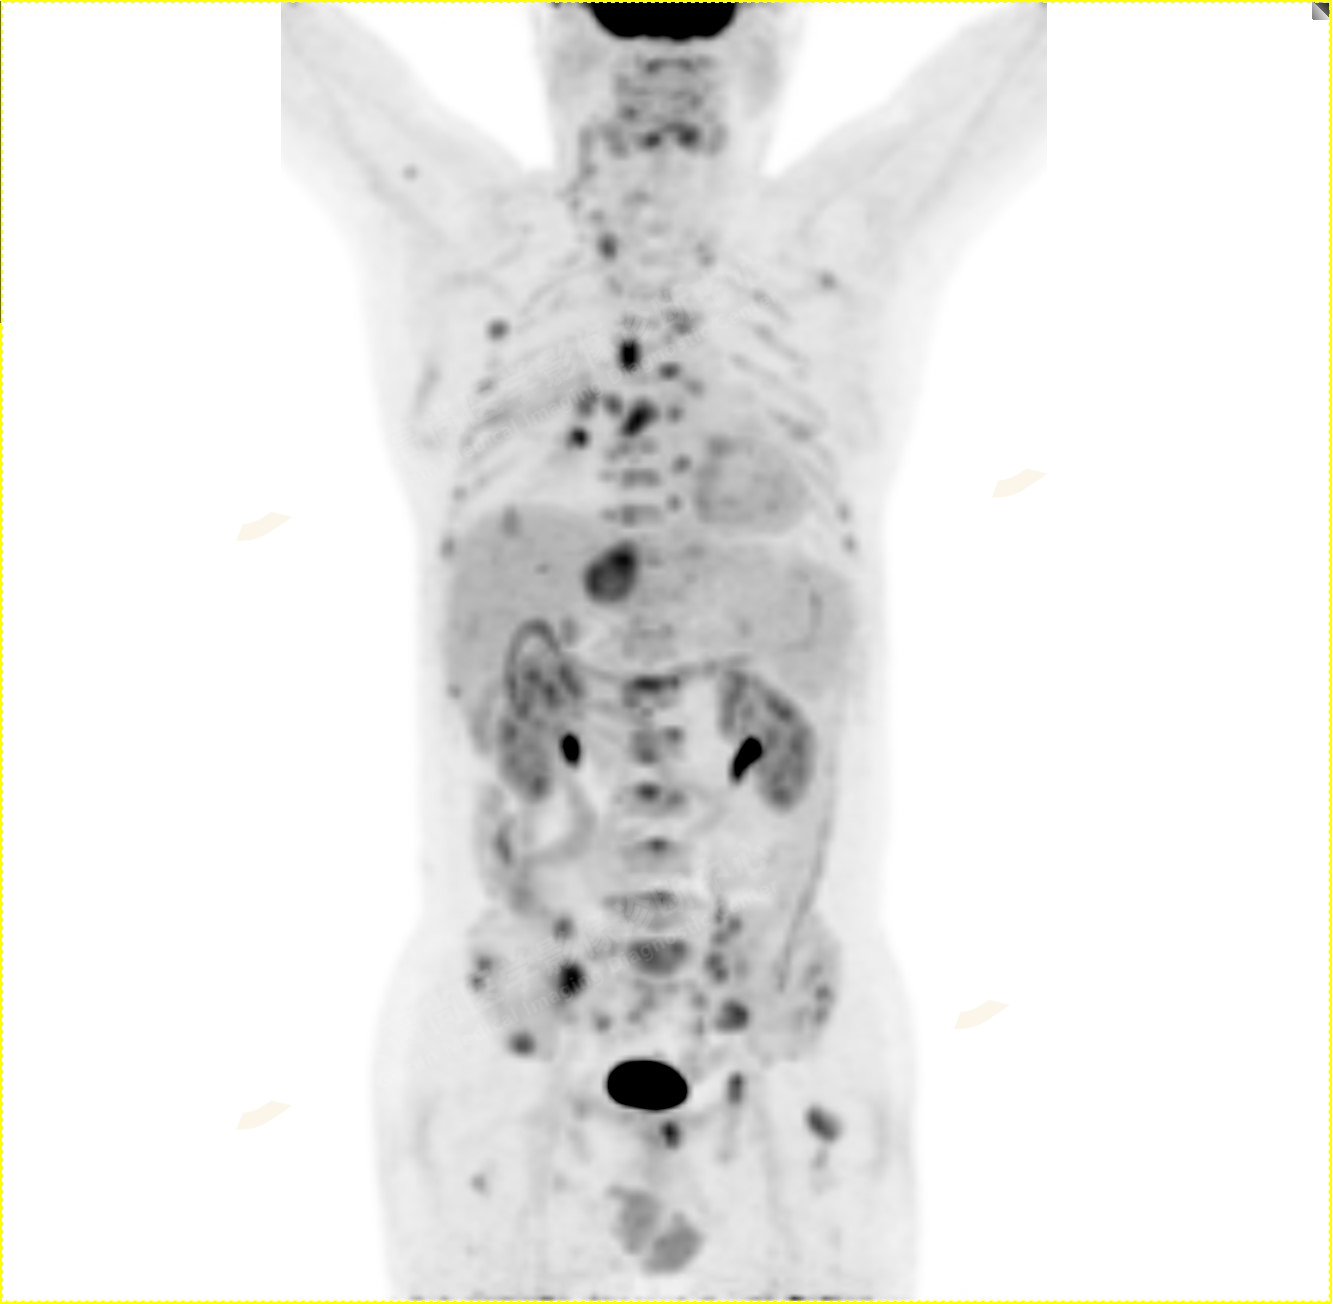

病史:男性,61歲,咳嗽1月余,CT發(fā)現(xiàn)肺結節(jié)。外院腋窩淋巴結穿刺活檢提示:轉移性腺癌。行PET/CT進行腫瘤分期。

1.右肺中葉內(nèi)側段軟組織結節(jié),呈淺分葉狀,邊緣可見毛刺及胸膜牽拉征,呈FDG代謝異常增高,考慮為周圍型肺癌。

2.雙肺內(nèi)彌漫性分布大小不等實性小結節(jié)灶及粟粒狀高密度影,均未見FDG代謝明顯異常增高,均多考慮為癌性淋巴結炎及轉移性病變。

3.右側頸部(Ⅱ-Ⅴ區(qū))、右側腋窩區(qū)、右側肺門及縱隔(1R、1L、2、4、6、7組)、肝門區(qū)多發(fā)腫大淋巴結,呈不同程度異常增高,均考慮為淋巴結轉移。

4.肝S4、8段團塊狀及結節(jié)狀低密度病變,以S4段病變?yōu)橹什煌潭菷DG代謝異常增高,考慮為肝多發(fā)轉移。

5.右側肱骨上段、左側肩胛骨、右側鎖骨胸骨端、胸骨、雙側多發(fā)肋骨、脊柱多發(fā)椎體及附件、雙側髂骨、雙側髖臼、雙側恥骨、雙側肱骨上段多發(fā)成骨性病變,呈不同程度FDG代謝異常增高,考慮為多發(fā)骨轉移瘤。

以上病變符合:T4N3M1c,ⅣB期(UICC/AJCC,2018年第8版肺癌TNM分期)。